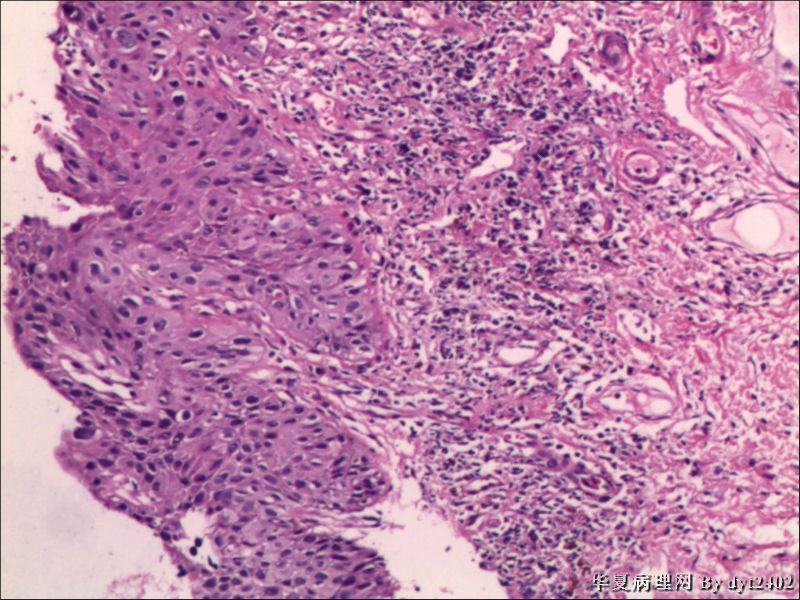

这样的外阴病变 发个原位癌是否合适?

图2